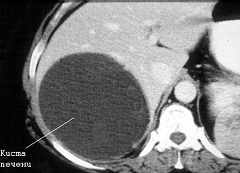

Кисты могут локализоваться в различных долях и сегментах печени, располагаться как в глубине органа, так и на его поверхности. В своем диаметре кисты печени достигают 25 сантиметров. Очень редко наблюдаются гигантские кисты, имеющие еще больший размер.

Истинные кисты печени возникают у человека еще в период внутриутробного развития. Причина их возникновения заключается в том, что некоторые желчные протоки оказываются неподключенными к общей системе желчных путей. Такие кисты обычно ничем себя не проявляют, и их обнаруживают обычно случайно при проведении компьютерной томографии или ультразвукового исследования печени по какому-либо другому поводу.